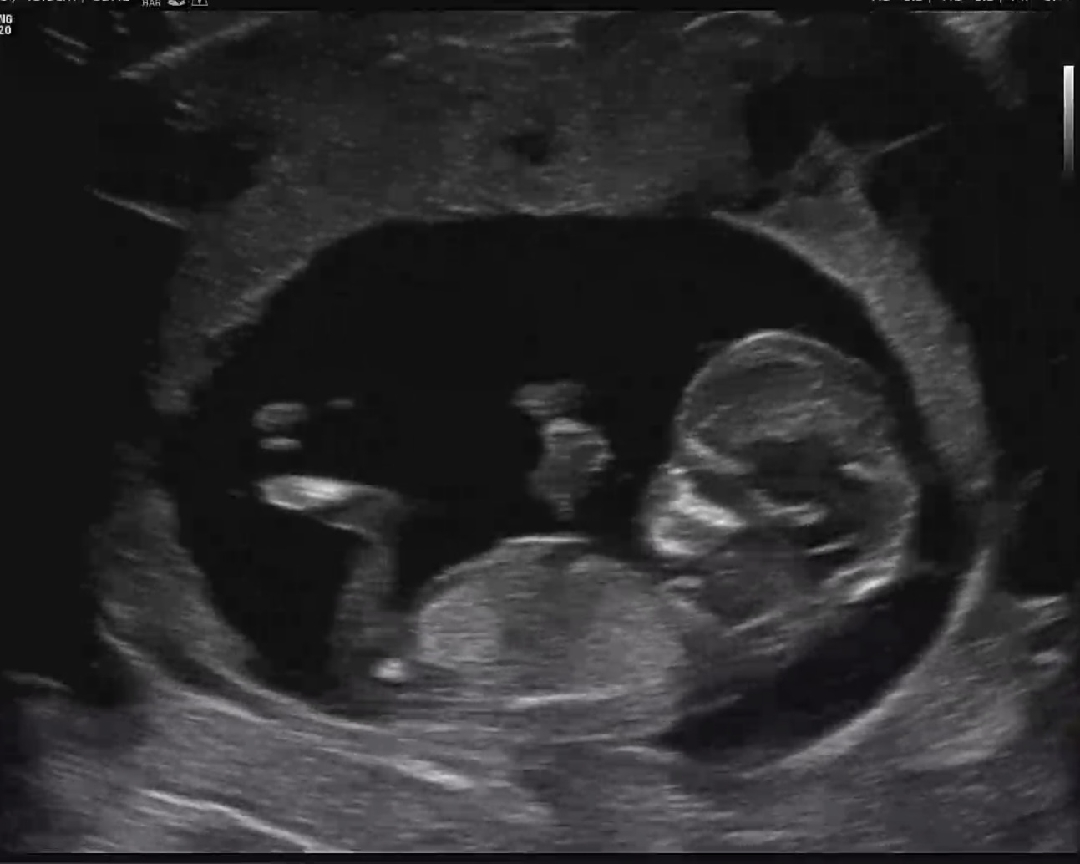

12주차 아들일까요? 딸일까요??^^

너무 궁금합니다 도와주세요~~~!

다리에 가려져서 안보입니당 ㅠ